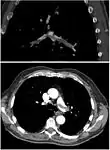

CT pulmonary angiography

CT pulmonary angiography (CTPA) is a pulmonary angiogram obtained using computed tomography (CT) with radiocontrast rather than right heart catheterization. Its advantages are that it is accurate, it is non-invasive, it is more often available, and it may identifying other lung disorders in case there is no pulmonary embolism. The accuracy and non-invasive nature of CTPA also make it advantageous for people who are pregnant.[57]

On CT scan, pulmonary emboli can be classified according to the level along the arterial tree.

Segmental and subsegmental pulmonary emboli on both sides

CT pulmonary angiography showing a "saddle embolus" at the bifurcation of the main pulmonary artery and thrombus burden in the lobar arteries on both sides.

Pulmonary embolism (white arrow) that has been long-standing and has caused a lung infarction (black arrow) seen as a reverse halo sign.

Assessing the accuracy of CT pulmonary angiography is hindered by the rapid changes in the number of rows of detectors available in multidetector CT (MDCT) machines.[58] According to a cohort study, single-slice spiral CT may help diagnose detection among people with suspected pulmonary embolism.[59] In this study, the sensitivity was 69% and specificity was 84%. In this study which had a prevalence of detection was 32%, the positive predictive value of 67.0% and negative predictive value of 85.2%. However, this study's results may be biased due to possible incorporation bias, since the CT scan was the final diagnostic tool in people with pulmonary embolism. The authors noted that a negative single slice CT scan is insufficient to rule out pulmonary embolism on its own. A separate study with a mixture of 4 slice and 16 slice scanners reported a sensitivity of 83% and a specificity of 96%, which means that it is a good test for ruling out a pulmonary embolism if it is not seen on imaging and that it is very good at confirming a pulmonary embolism is present if it is seen. This study noted that additional testing is necessary when the clinical probability is inconsistent with the imaging results.[60] CTPA is non-inferior to VQ scanning, and identifies more emboli (without necessarily improving the outcome) compared to VQ scanning.[61]